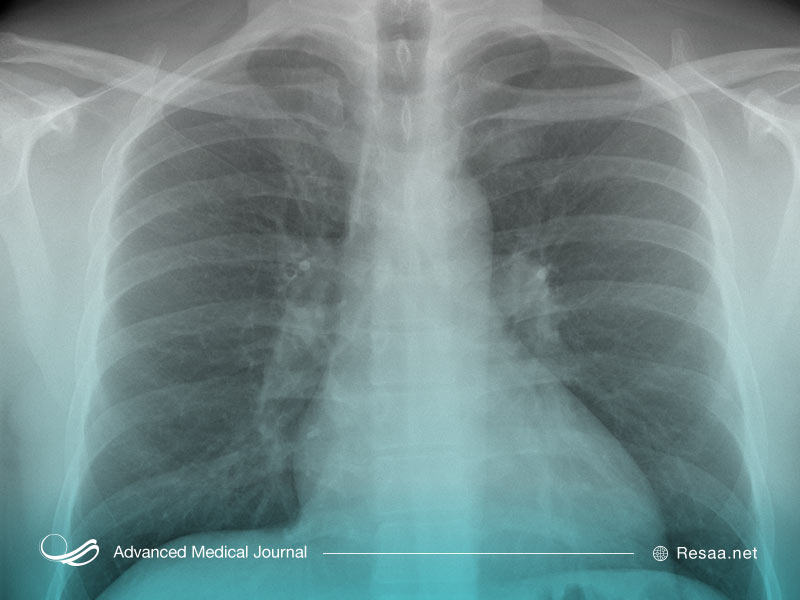

این تصاویر به وسیله اشعه ایکس یا اسکن تصویری از اندامها و ساختارها (قلب، ریهها و مجاری هوایی) در قفسه سینه تولید میشود. تصاویر به دست آمده انسداد، التهاب و مایعات اضافی را تشخیص میدهند.

اشعه ایکس (رادیوگرافی “radiography”).

از مقادیر حداقل تابش یا اشعه به منظور تولید یک تصویر دو بعدی استفاده میکند. این روشها معمولاً در بیمارستانها و با استفاده از تجهیزات ثابت توسط متخصص رادیولوژی انجام میشوند اما ممکن است با استفاده از دستگاههای قابل حمل نیز انجام شوند.

به طور متوسط CT اسکن قفسه سینه در 93٪ افراد مبتلا به COVID-19، عفونت تایید شده را به درستی شناسایی کرده است (65 مطالعه، 5759 نفر). اشعه ایکس “X-ray” قفسه سینه در 82٪ افراد مبتلا به کووید 19، عفونت تأیید شده را به درستی شناسایی کرده است (9 مطالعه، 682 نفر). سونوگرافی ریه یا اولتراسوند در 100٪ افراد مبتلا به کرونا ویروس، عفونت تأیید شده را به درستی تشخیص داده است (2 مطالعه، 32 نفر).

شواهد نشان میدهد که CT قفسه سینه و اشعه ایکس قفسه سینه آزمایشهای خوبی به منظور تایید و تشخیص کرونا در افرادی که عفونتشان با استفاده از آزمایشهای دیگر تشخیص داده شده، هستند. با این حال سی تی اسکن ممکن است در تأیید یا رد عفونت در افرادی که به COVID-19 مشکوک هستند، دقت کمتری داشته باشد.

- CT یا اشعه ایکس قفسه سینه نمیتواند با دقت بالایی بین COVID-19 و سایر عفونتهای تنفسی مانند آنفلوانزای فصلی تفاوت قائل شود. برخلاف آزمایشهای سواب “swab” که منجر به تشخیصهای خاص COVID-19 میشود، یافتههای تصویربرداری برای تأیید COVID-19 به اندازه کافی دقیق نیستند. آنها میتوانند فقط به علائم عفونت اشاره کنند. این علائم میتواند به دلایل دیگری از جمله آنفلوانزای فصلی یه وجود آمده باشند که در بعضی از فصول سال بسیار شایع است.

- درصد قابل توجهی از بیماران مبتلا به COVID-19، سی تی اسکن و تصویر قفسه سینه طبیعیای دارند. برای آن دسته از بیماران، یک نتیجه تصویربرداری طبیعی میتواند به دروغ، آنها را متقاعد کند که سالم هستند. اگر آنها معتقد باشند که سالم هستند، دیگران را در معرض ابتلا به ویروس کرونا قرار میدهند.

اگرچه سی تی اسکن و اشعه ایکس به عنوان تنها راه تشخیص COVID-19 توصیه نمیشود اما ممکن است به صورت موردی مناسب باشد. در بیماران با علائم شدید ممکن است تصویربرداری به ارزیابی جدی بودن بیماری کمک کند. هنگامی که از آزمایشات آزمایشگاهی، سابقه کامل پزشکی و معاینه فیزیکی استفاده میشود، سی تی اسکن یا اشعه ایکس میتواند به منظور تعیین برنامه مراقبت از بیمار مفید باشد.

به طور کلی تصویربرداری در مدیریت بیماران مبتلا به COVID-19 نقش مکمل را دارد. سی تی اسکن قفسه سینه به عنوان تنها ابزار غربالگری بیماری توصیه نمیشود. در حال حاضر آزمایشات آزمایشگاهی، دقیقترین روش تشخیص این بیماری است.